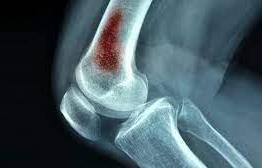

מטופלים שהתמודדו עם זיהום בעצם או במפרק (למשל אוסטאומיאליטיס או דלקת מפרקים זיהומית) אשר הוביל לנזק ברקמה, לחולשה ממושכת או להגבלת תנועה. שיקום פיזיקלי במקרה כזה נועד לעזור בבנייה מחודשת של הכוח והיציבות באזור הפגוע לאחר שהזיהום טופל רפואית. נתמקד בעבודה איטית וזהירה על חיזוק השרירים סביב המקום שנפגע, בשיפור טווח התנועה שנפגע עקב תקופת אי-השימוש בזמן המחלה, ובמניעת פציעות נוספות עקב חולשת האזור.

השיקום במקרים אלו מתבצע בתיאום צמוד עם הרופאים, כדי לוודא שהאזור החלים מהזיהום ושהטיפול הפיזי בטוח ומתאים למצב הרפואי.